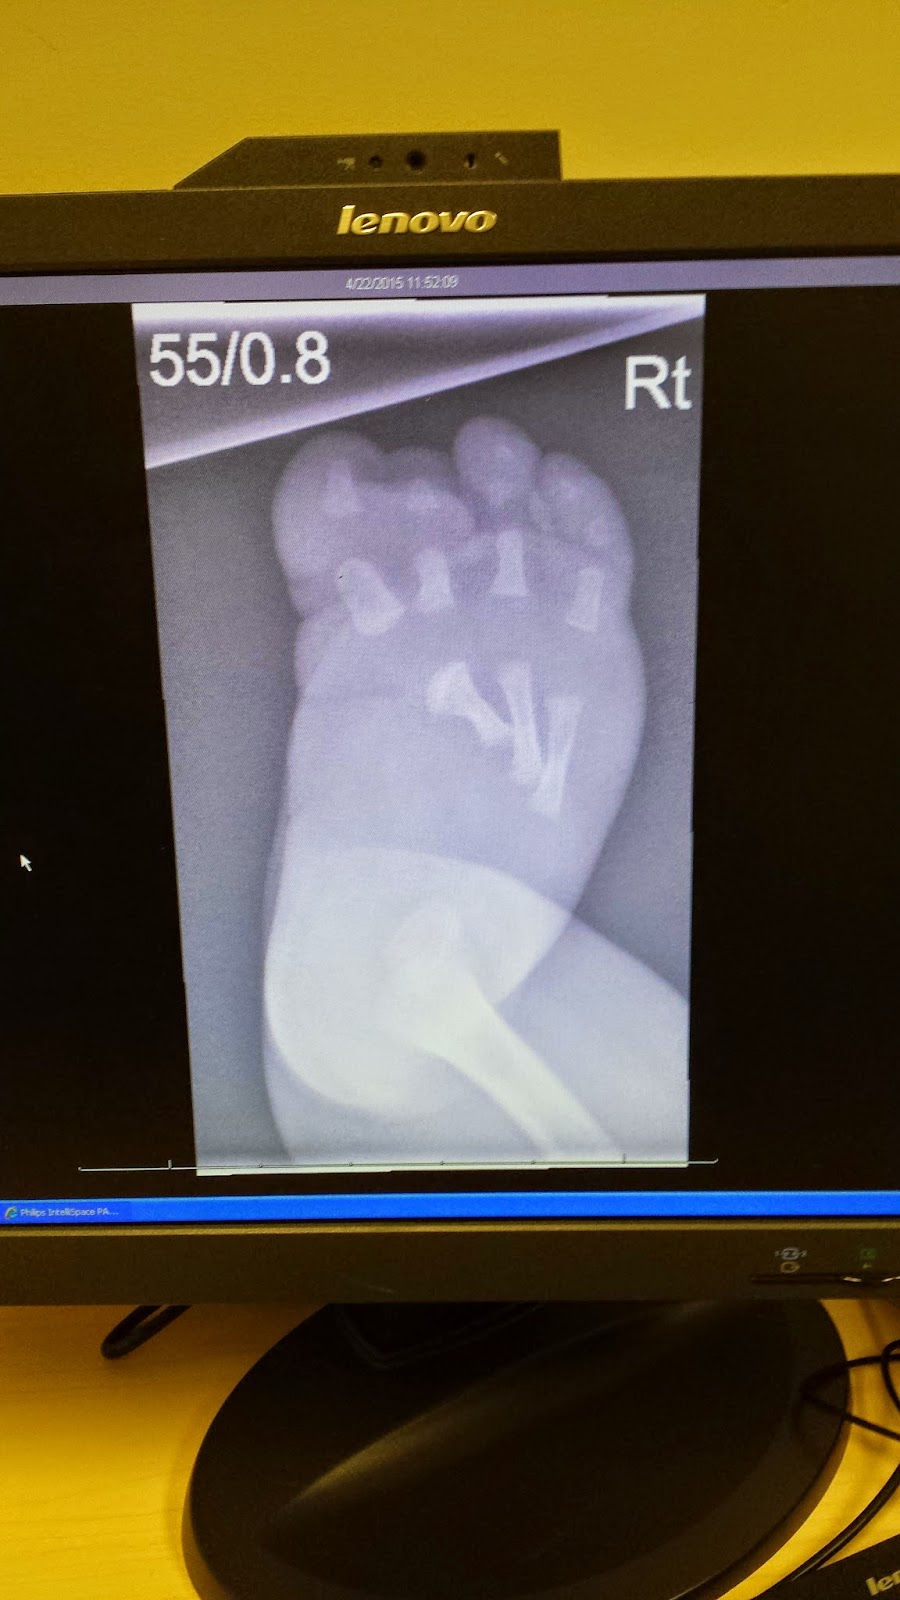

Joelle's right foot x-ray. You can see she is missing a toe and her bones are quite out.

Getting the x-rays was a tad difficult. J moved around so much they had to use so much velcro and tape to keep her still. She screamed and didn't like it at all.